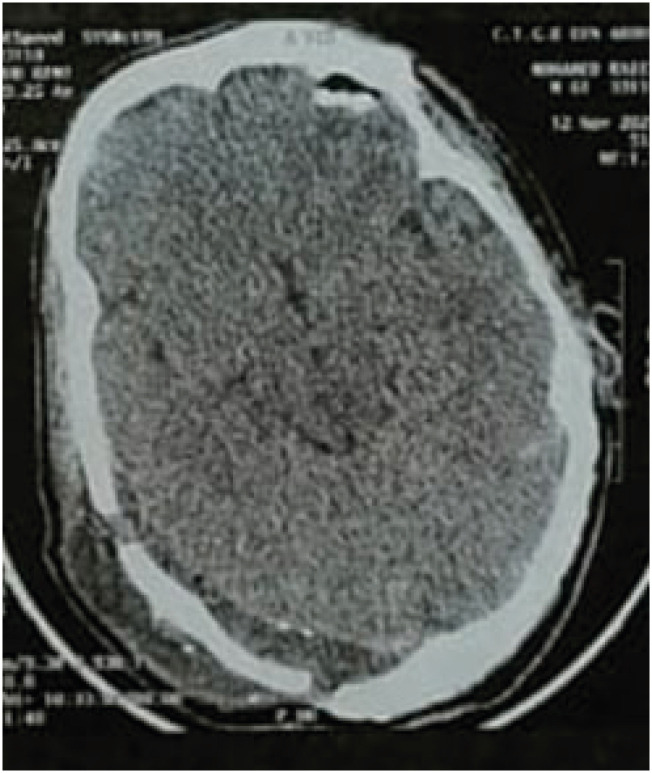

Abstract Image